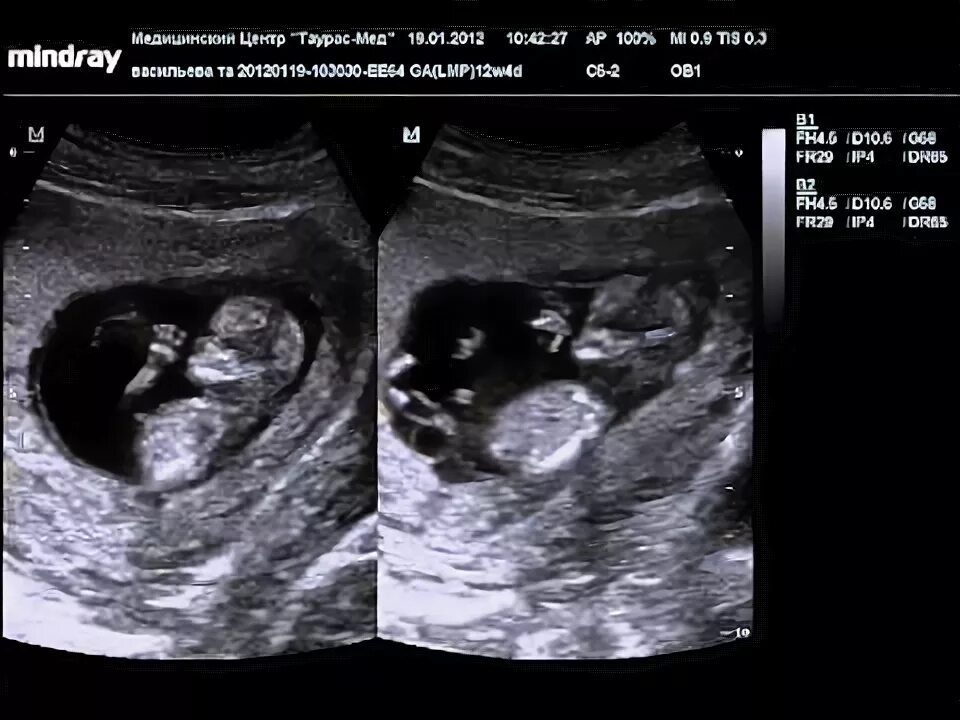

Как определить пол ребенка 12 недель